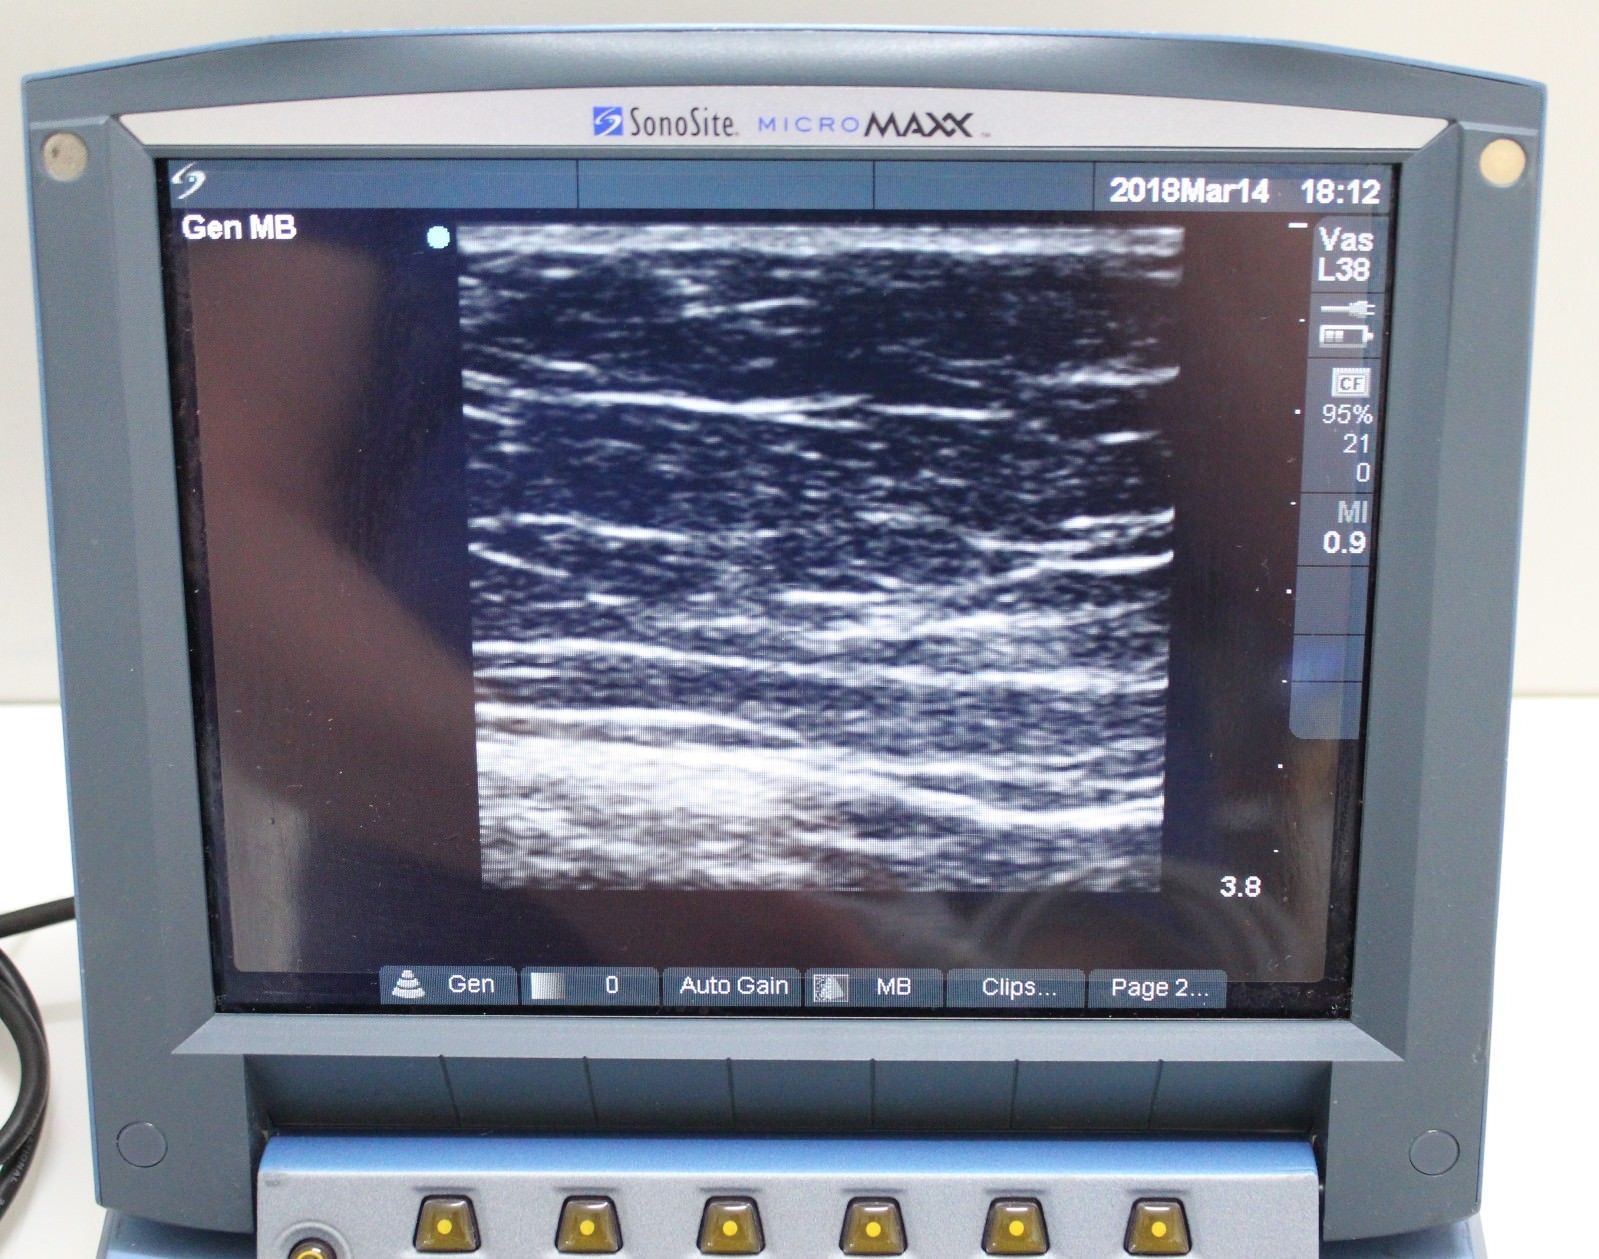

Brand: Sonosite

Model: Micromaxx